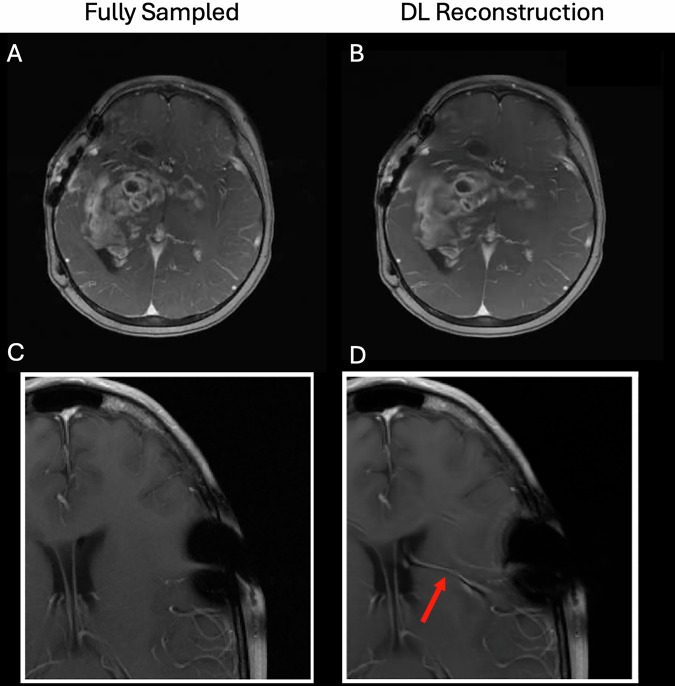

Given the enormous output and pace of development of artificial intelligence (AI) methods in medical imaging, it can be challenging to identify the true success stories to determine the state-of-the-art of the field. This report seeks to provide the magnetic resonance imaging (MRI) community with an initial guide into the major areas in which the methods of AI are contributing to MRI in oncology. After a general introduction to artificial intelligence, we proceed to discuss the successes and current limitations of AI in MRI when used for image acquisition, reconstruction, registration, and segmentation, as well as its utility for assisting in diagnostic and prognostic settings. Within each section, we attempt to present a balanced summary by first presenting common techniques, state of readiness, current clinical needs, and barriers to practical deployment in the clinical setting. We conclude by presenting areas in which new advances must be realized to address questions regarding generalizability, quality assurance and control, and uncertainty quantification when applying MRI to cancer to maintain patient safety and practical utility.